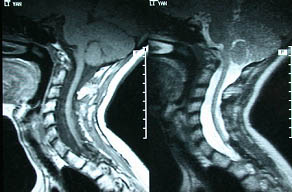

术前术后照片对比